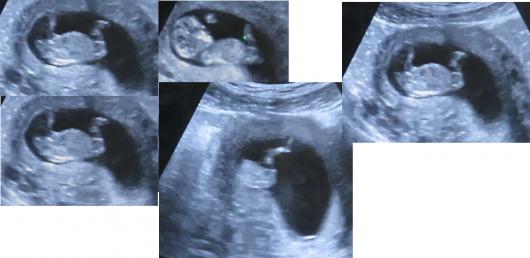

Hi, my wife is 12 weeks, I made a movie from the ultrasound and I found some frames in which I think I see the NUB. Am I right that we are expecting a girl?Attachment 31387

The pictures are small so it's a bit hard to tell but that does look like a girly nub.

It looks girly, especially if the gestation is 12w4d +. If it is 12w exactly it could rise but still looks quite girly.

No it is only 11 weeks 5 days. Unfortunately we don't have another ultrasound until 20 weeks

I'm sorry but it's very early for a guess at this gestation. Before 12w it's not valid at all.